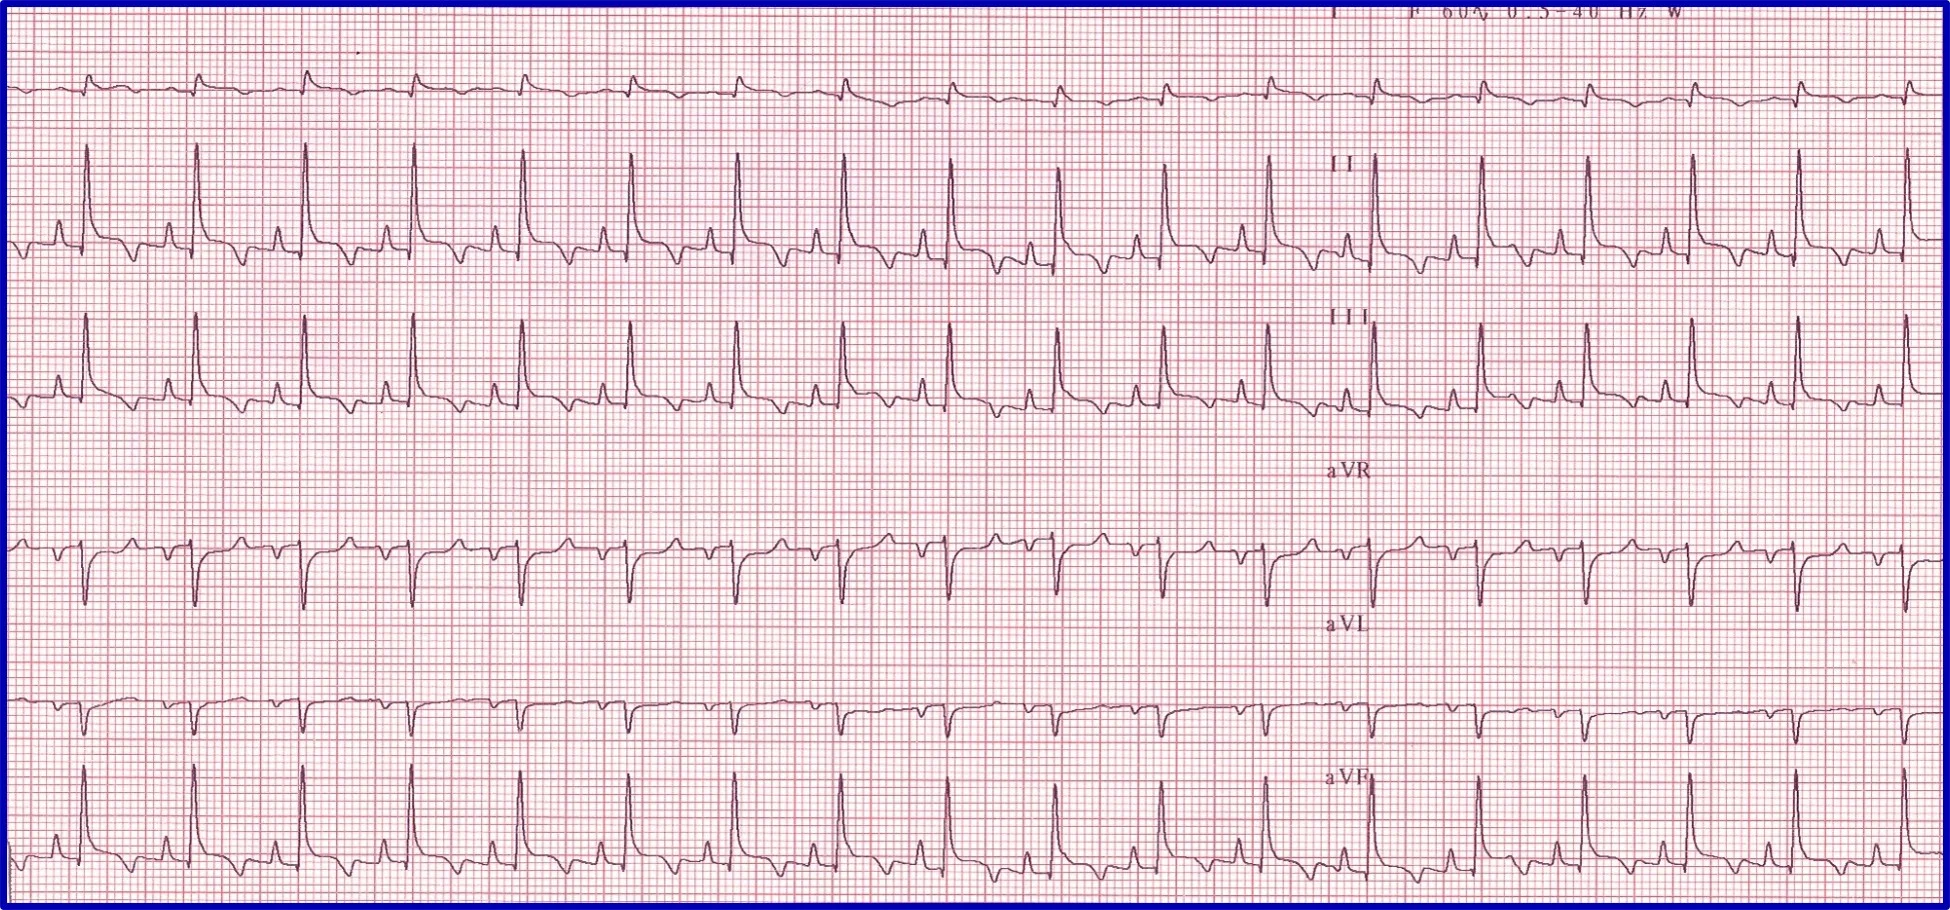

Evaluation of an arrhythmia with AV nodal disease includes determination of whether the arrhythmia is hemodynamically important (ie, rhythm is slow enough to cause clinical signs, including exercise intolerance, syncope, and signs of congestive heart failure) and whether there is autonomic influence on the arrhythmia that can be accomplished with administration of a high-end dose of atropine (0.04 mg/kg SC or IM). Expected response for a normal sinus or AV node with excessive vagal influence is complete resolution of the AV block and a heart rate >160 to 180 bpm (Figure 5).

(A) ECG in a patient with high-grade second-degree AV block in which no 2 consecutive P waves are conducted to create ventricular depolarization. Each QRS complex has a P wave with a constant PR interval, but many P waves do not have an accompanying QRS complex. (B) Thirty minutes after administration of atropine (0.04 mg/kg IM), ECG showed complete resolution of the AV block, 1:1 conduction of every P wave, and heart rate >180 bpm, indicating the SA and AV nodes are fully functional and the prior delay in conduction was vagally mediated.